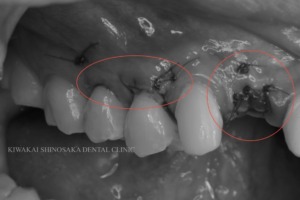

その後、主訴である右上2の歯肉の厚さを増やすため、【結合組織移植手術(CTG)】を行いました。

また、歯茎下りによって右上4・5の歯の根が少し露出しており、滲みるなどの症状がみられましたので、同日に右上4・5への【結合組織移植を併用した根面被覆術】も行いました。

移植する結合組織は上顎から採取します。